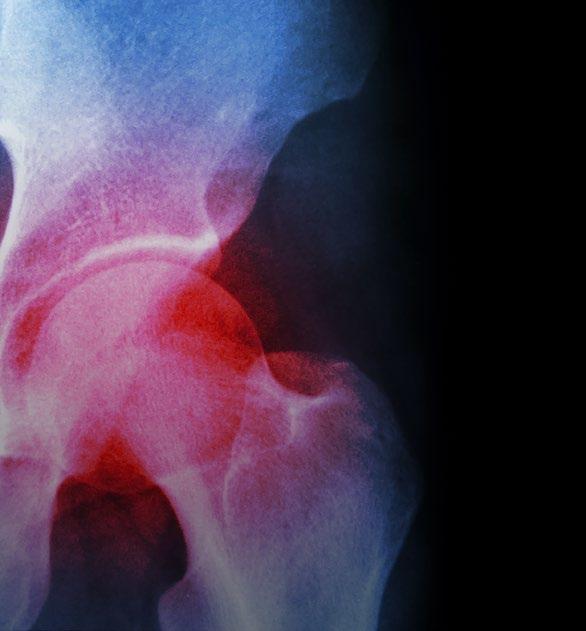

Arthrose ist in Deutschland wie in allen Industrienationen die häufigste Gelenkerkrankung. Hüftarthrose stellt hierbei mit einer Inzidenz von 5% über 65 Jahre die häufigste Ursache für eine eingeschränkte Mobilität dar. Demzufolge werden in Deutschland ca. 200.000 Ersatzoperationen des Hüftgelenks pro Jahr durchgeführt. Die Hüftarthrose (Coxarthrose) beschreibt ein sehr heterogenes Krankheitsbild mit einer gemeinsamen Endstrecke einer terminalen Gelenkknorpeldestruktion und weiteren Veränderungen der umgebenden Gewebe.

Eine den Destruktionsprozess begleitende Entzündung bewirkt durch eine chronische Synovitis (Gelenkschleimhautentzündung) eine Verdickung der Kapsel und führt neben den genannten Gelenksanbauten zu einer verminderten Beweglichkeit der Hüfte und damit zu einer eingeschränkten Funktion. Diese gestörte Kinematik der Hüfte, gepaart mit meist einseitig vermehrtem Abrieb des Knorpels, verstärkt den Prozess der Bewegungsstörung, wodurch wiederum die Destruktion beschleunigt wird.

Ischiadicus-Affektion zu nennen. Auch Leistenbeschwerden bei einer Hernie (Leistenbruch) müssen abgegrenzt werden, wobei die Beteiligung der Leiste eine hohe Korrelation mit dem Vorliegen einer Hüftarthrose aufweist. Diagnostiziert wird eine Hüftarthrose durch die klinische Untersuchung und bildgebende Diagnostik. Hier wären die Kernspintomographie und das konventionelle Röntgen bei höhergradiger Arthrose die Mittel der Wahl. Die Säulen der Therapie der Hüftarthrose sind der Funktionserhalt und die Schmerzreduktion. Im Vergleich zur Kniearthrose liegen relativ wenige randomisierte Studien zur Differenzierung von medikamentöser und nichtmedikamentöser Therapie vor. Wenngleich eine Verbesserung der klinischen Situation erzielt werden kann, so ist die Erfolgsrate geringer als bei der Kniearthrose und der Zeitraum des Behandlungserfolgs verkürzt.